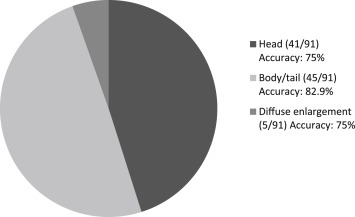

Among the 268 patients, 233 patients with successful FNA procedures for solid tumors (98 women, 135 men) with verified clinical outcome for review were included in this study. These patients were classified according to the anatomic location of the lesions as pancreatic tumors (Group A, n = 91), mediastinal tumors (including lymph node) (Group B, n = 38), abdominal tumorous lesions (including lymph node) (Group C, n = 49), focal transmural thickening of the GI tract (Group D, n = 6, all were with nonspecific diagnosis from endoscopic biopsy), submucosal tumors of the GI tract (Group E, n = 49) ( Table 1 ; Fig. 2 ). The accuracies of pathological diagnosis of malignancy were 79.2%, 76.9%, 93.2%, and 80% for groups A–D, respectively. The respective sensitivity, specificity, PPV, NPV are also shown (Table 2 ). The respective proportion of the pancreatic tumors according to the different locations and their diagnostic accuracies are shown in Fig. 3 . In total, for all of these lesions, the overall accuracy for the diagnosis of malignancy was 82.9%. For the stromal tumors of the GI tract in Group E (all originating from below the submucosal layer), FNA cytopathology showed evidence of specific diagnosis of GIST in all (47%) of these cases, 14% were diagnosed as suspicious (most were of a spindle cell tumor nature, except for one adenocarcinoma) and 39% were considered negative for tumor or non-diagnostic. For the patients with negative or non-diagnostic FNA cytopathology, none were found to have an outcome of malignancy progression or tumor-related morbidity/mortality (Fig. 3 ).

Figure 3. Number, proportion, and diagnostic accuracies of endoscopic ultrasound-guided fine needle aspiration (EUS-FNA) for the pancreatic tumor according to the different tumor locations. |

The study results show that the yield of punctures differed according to the lesions with location of the puncture and the pathological nature. The best diagnostic yields were from the aspiration of enlarged lymph nodes or tumors from the intra-abdominal region. Pancreatic tumors constituted the largest proportion of the targets of EUS-FNA because most suspected pancreatic malignancies were out of the range of surgical resection. Tissue diagnosis is thus important for further management. The accuracy of EUS-FNA for pancreatic tumors overall was 79.2%. The accuracy was better for tumors over the body or tail of the pancreas (82.9%), but was relatively lower (75%) for tumors on the pancreatic head, especially the uncinate process. The relatively low yield rate may have been due to necrosis inside the tumor and technical difficulty on this area. Performing puncture for the pancreatic head lesions, especially the uncinate process, was the most difficult, because a certain amount of bending and twisting of the echoendoscope is needed to correctly position the instrument for puncture and this brings considerable resistance for the needle to extrude from the sheath. The pushing force, thus, cannot be transmitted to the needle from the proximal handle [11] . In some cases, collateral vessels were seen around the pancreatic head due to the compression or invasion of the tumor and this hindered the access of the needle. In fact, three of five patients with EUS-FNA failure had pancreatic head lesions.